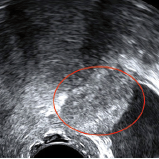

QUIZZ IMAGE 190

Une image à chaque étage par Joël Créquat Contexte cliniquePatiente de 35 ans sans enfant et sans antécédent particulier.Elle n’a pas de contraception. Elle consulte pour dysménorrhée, algies diffuses, dyspareunie progressive, et dysurie menstruelle d’apparition récente.L’examen clinique retrouve une masse annexielle droite, vraisemblablement ovarienne et une sensibilité pelvienne générale.Une échographie est demandée. Voici les résultats…